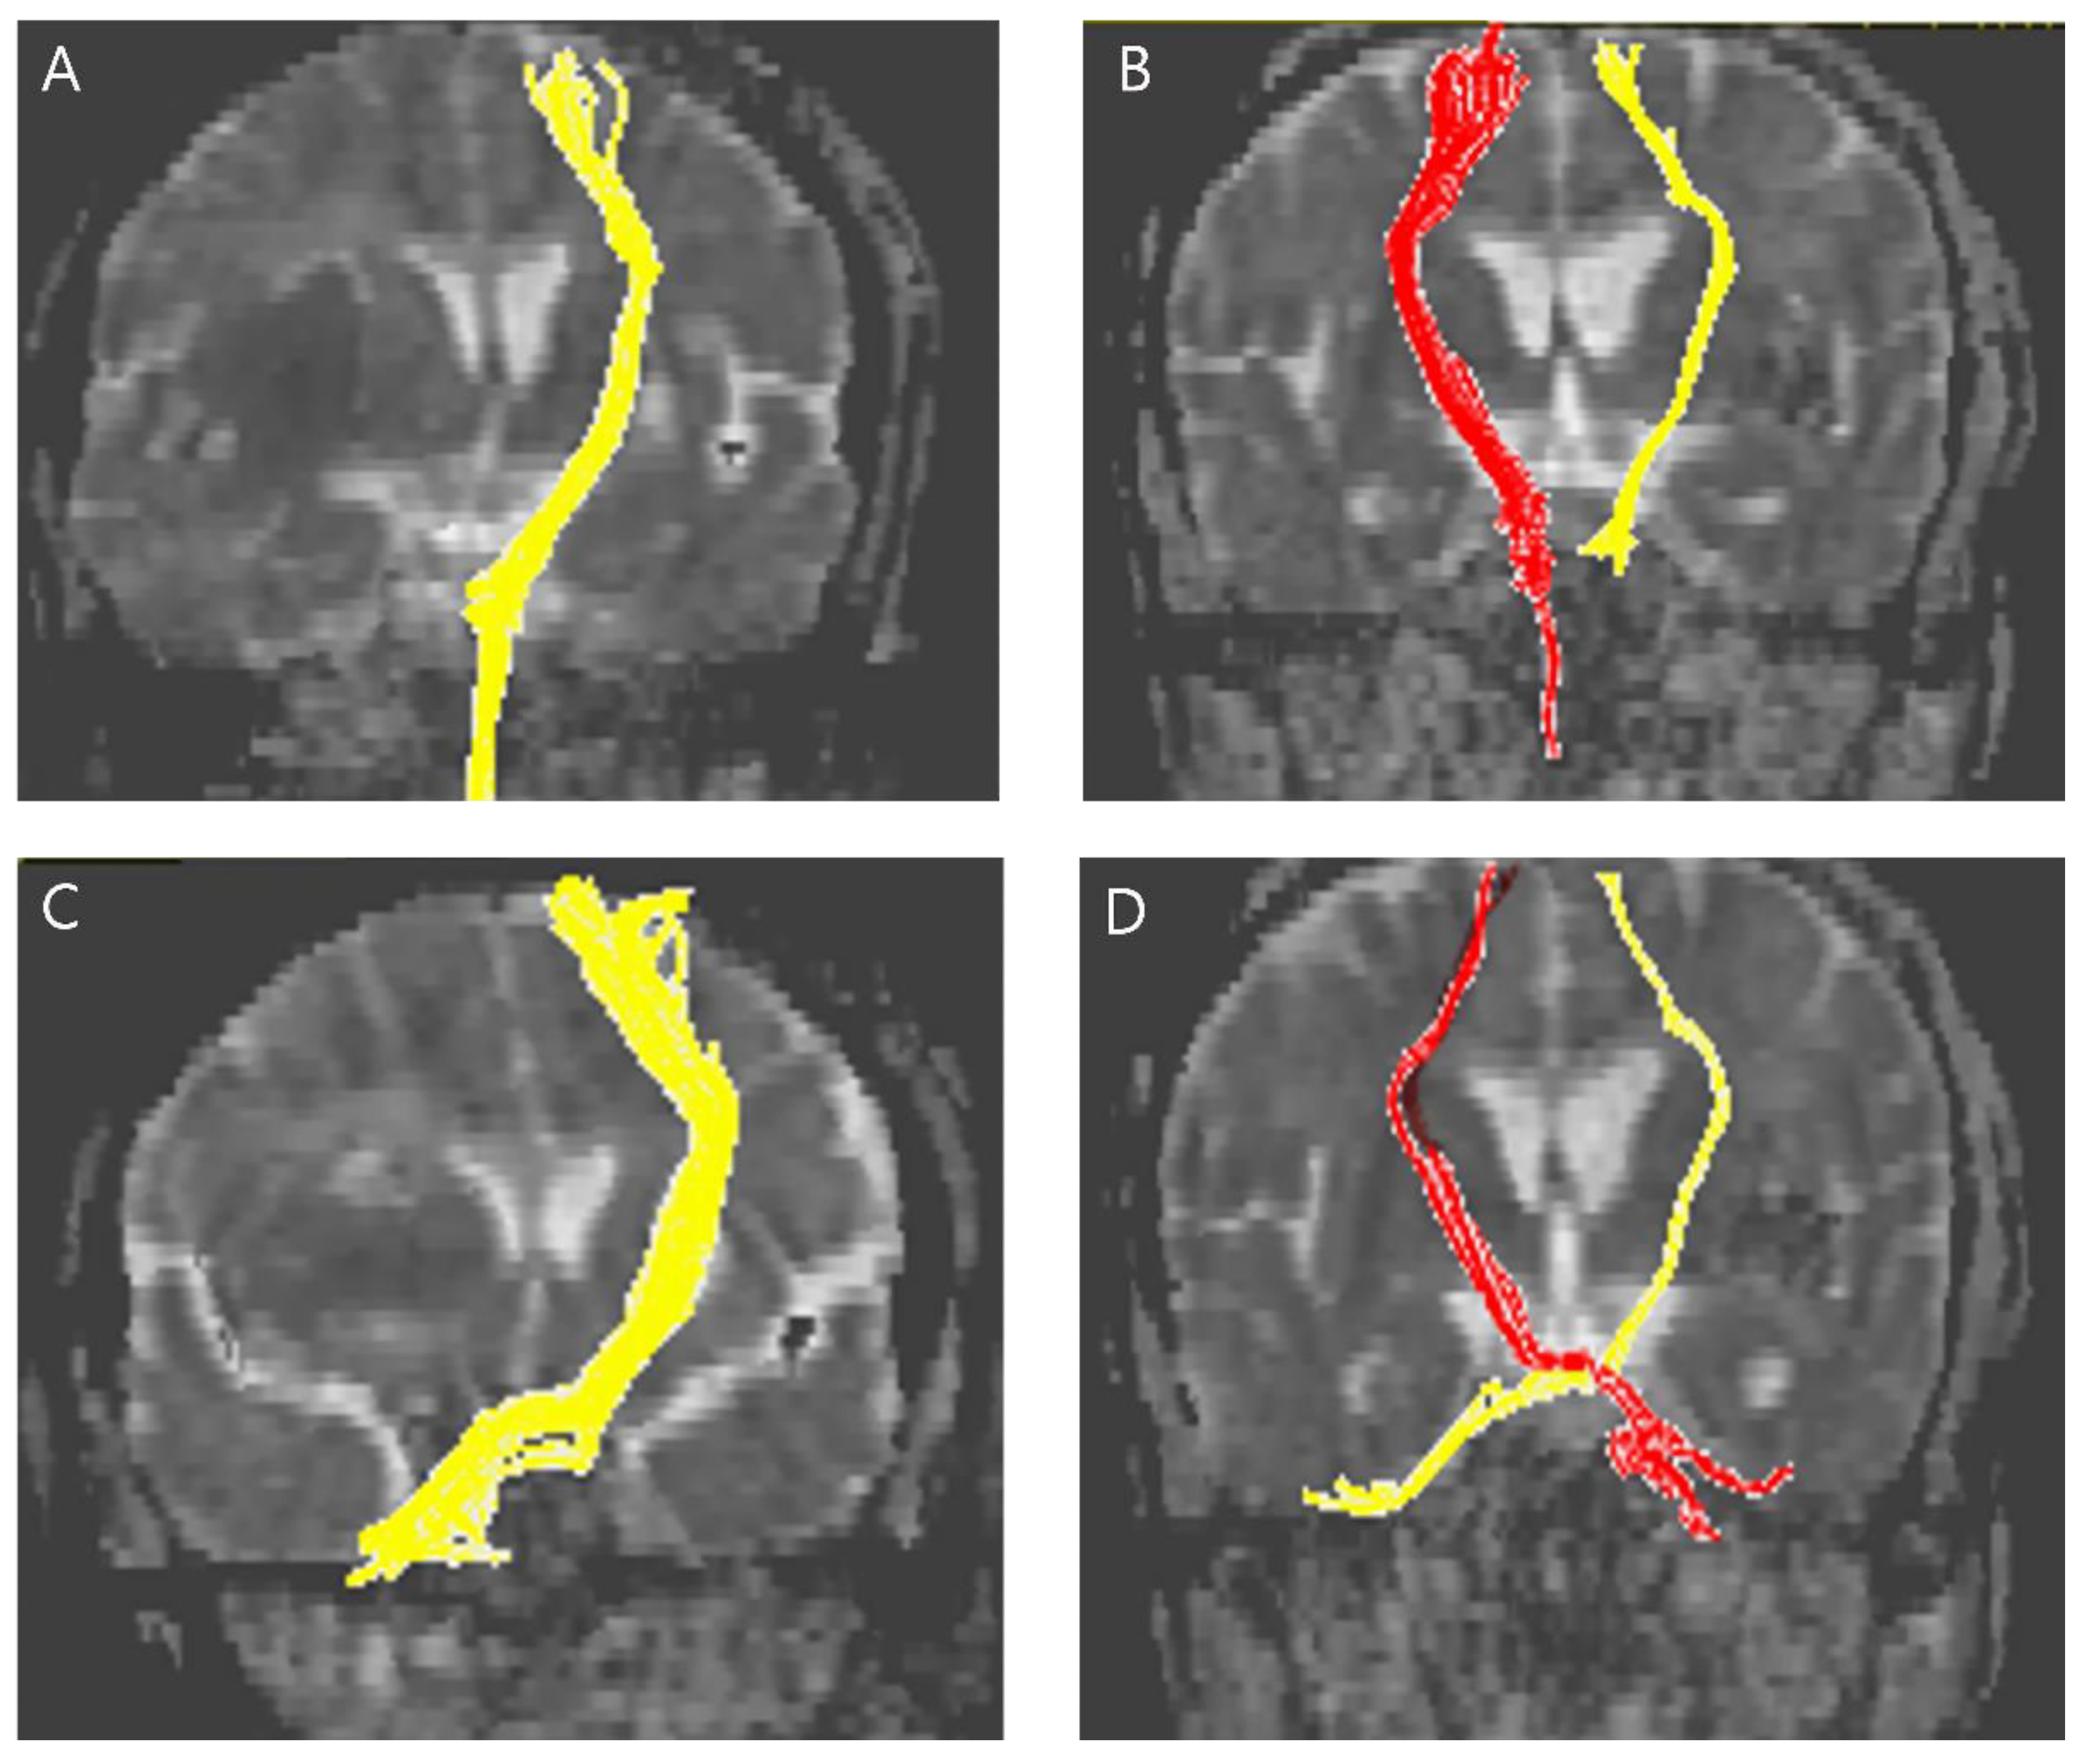

The normalized FA and FN values in the CPCT were significantly higher in the good hand function group than in the poor hand function group (FN 25.240 and 0.587 respectively, p = 0.021; FA 0.985 and 0.459 respectively; p = 0.015) (Figure 2). The normalized FN and FA in the CST were not significantly different between the poor hand function group and the good hand function group. Representative DTIs of the CST and CPCT for the two groups are presented in Figure 3.

Figure 3.

Representative diffusion tensor tractography images of the CST in typical subjects from the (A) poor hand function group and the (B) good hand function group. The non-affected tract is shown in yellow in (A) and red in (B). Representative diffusion tensor tractography images of the CPCT in typical subjects from the (C) poor hand function group and the (D) good hand function group. The non-affected tract is shown in yellow in (C) and red in (D).